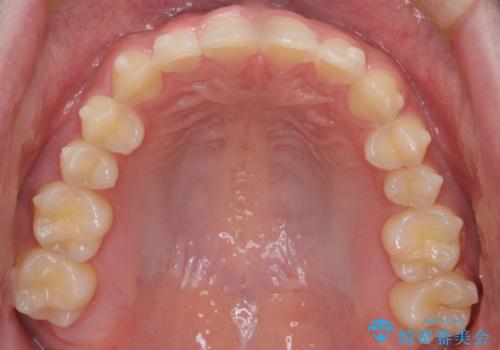

【インビザライン】前歯のガタガタと、前歯の噛み合わせが深いことを治したい。

- 前歯のガタガタと、前歯の噛み合わせが深いことを治したい。との主訴で来院されました。

シミュレーションを用いながら患者様と仕上がりについて相談しインビザラインにて治療を行いました。

仕上げは追加アライナーを数回利用しておこないました。